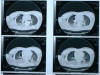

MO Distres respiratorio del adulto por trauma.